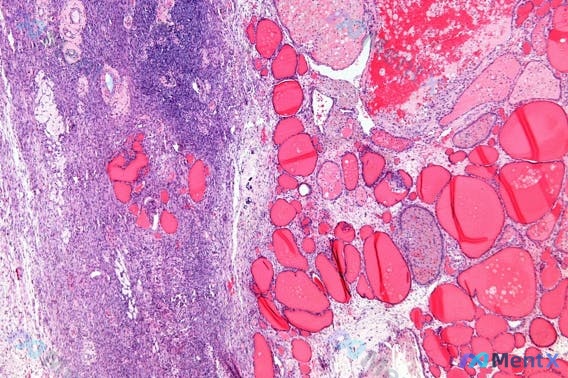

无坏死肉芽肿伴发热消瘦,初始治疗敢直接上激素吗?

整理了一个肉芽肿性病变病例,大家聊聊初始处理思路: 基本情况:44岁女性,6个月疲劳、间歇性发热、体重减轻4kg,伴进行性干咳,不抽烟。 体格检查:双侧肺野轻度喘息,锁骨上+颈部淋巴结肿大,已做胸部CT,颈部淋巴结活检提示「有组织的上皮样组织细胞和多核巨细胞,无局灶性坏死」。 问题来了:这个情况初始...